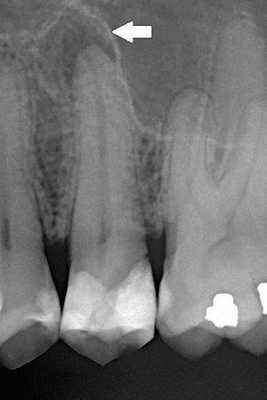

Перед препарированием следует получить внутриротовые снимки, позволяющие в какой-то степени составить представление о величине полости зуба и положении рогов пульпы.

Хронические формы периодонтита в большинстве случаев протекают бессимптомно и выявляются во время рентгенологического исследования либо при обострении.